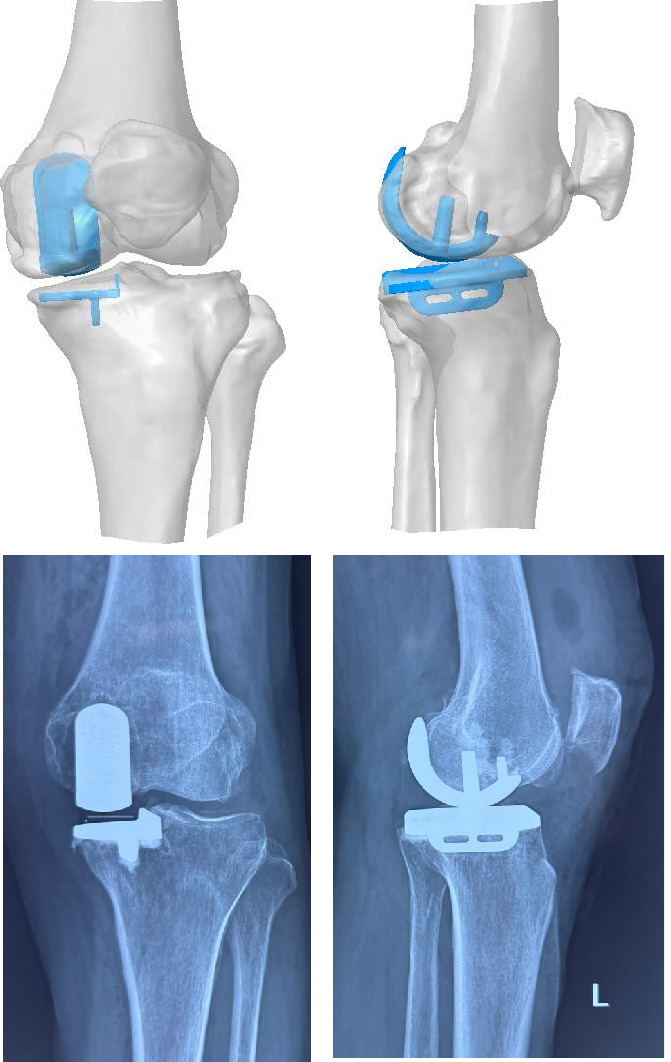

图片

不同案例——术前模拟图和术后X光片对比